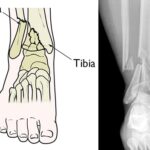

Plantar plate tears are diagnosed with a physical exam, medical history and X-rays. An MRI or ultrasound may also be used.